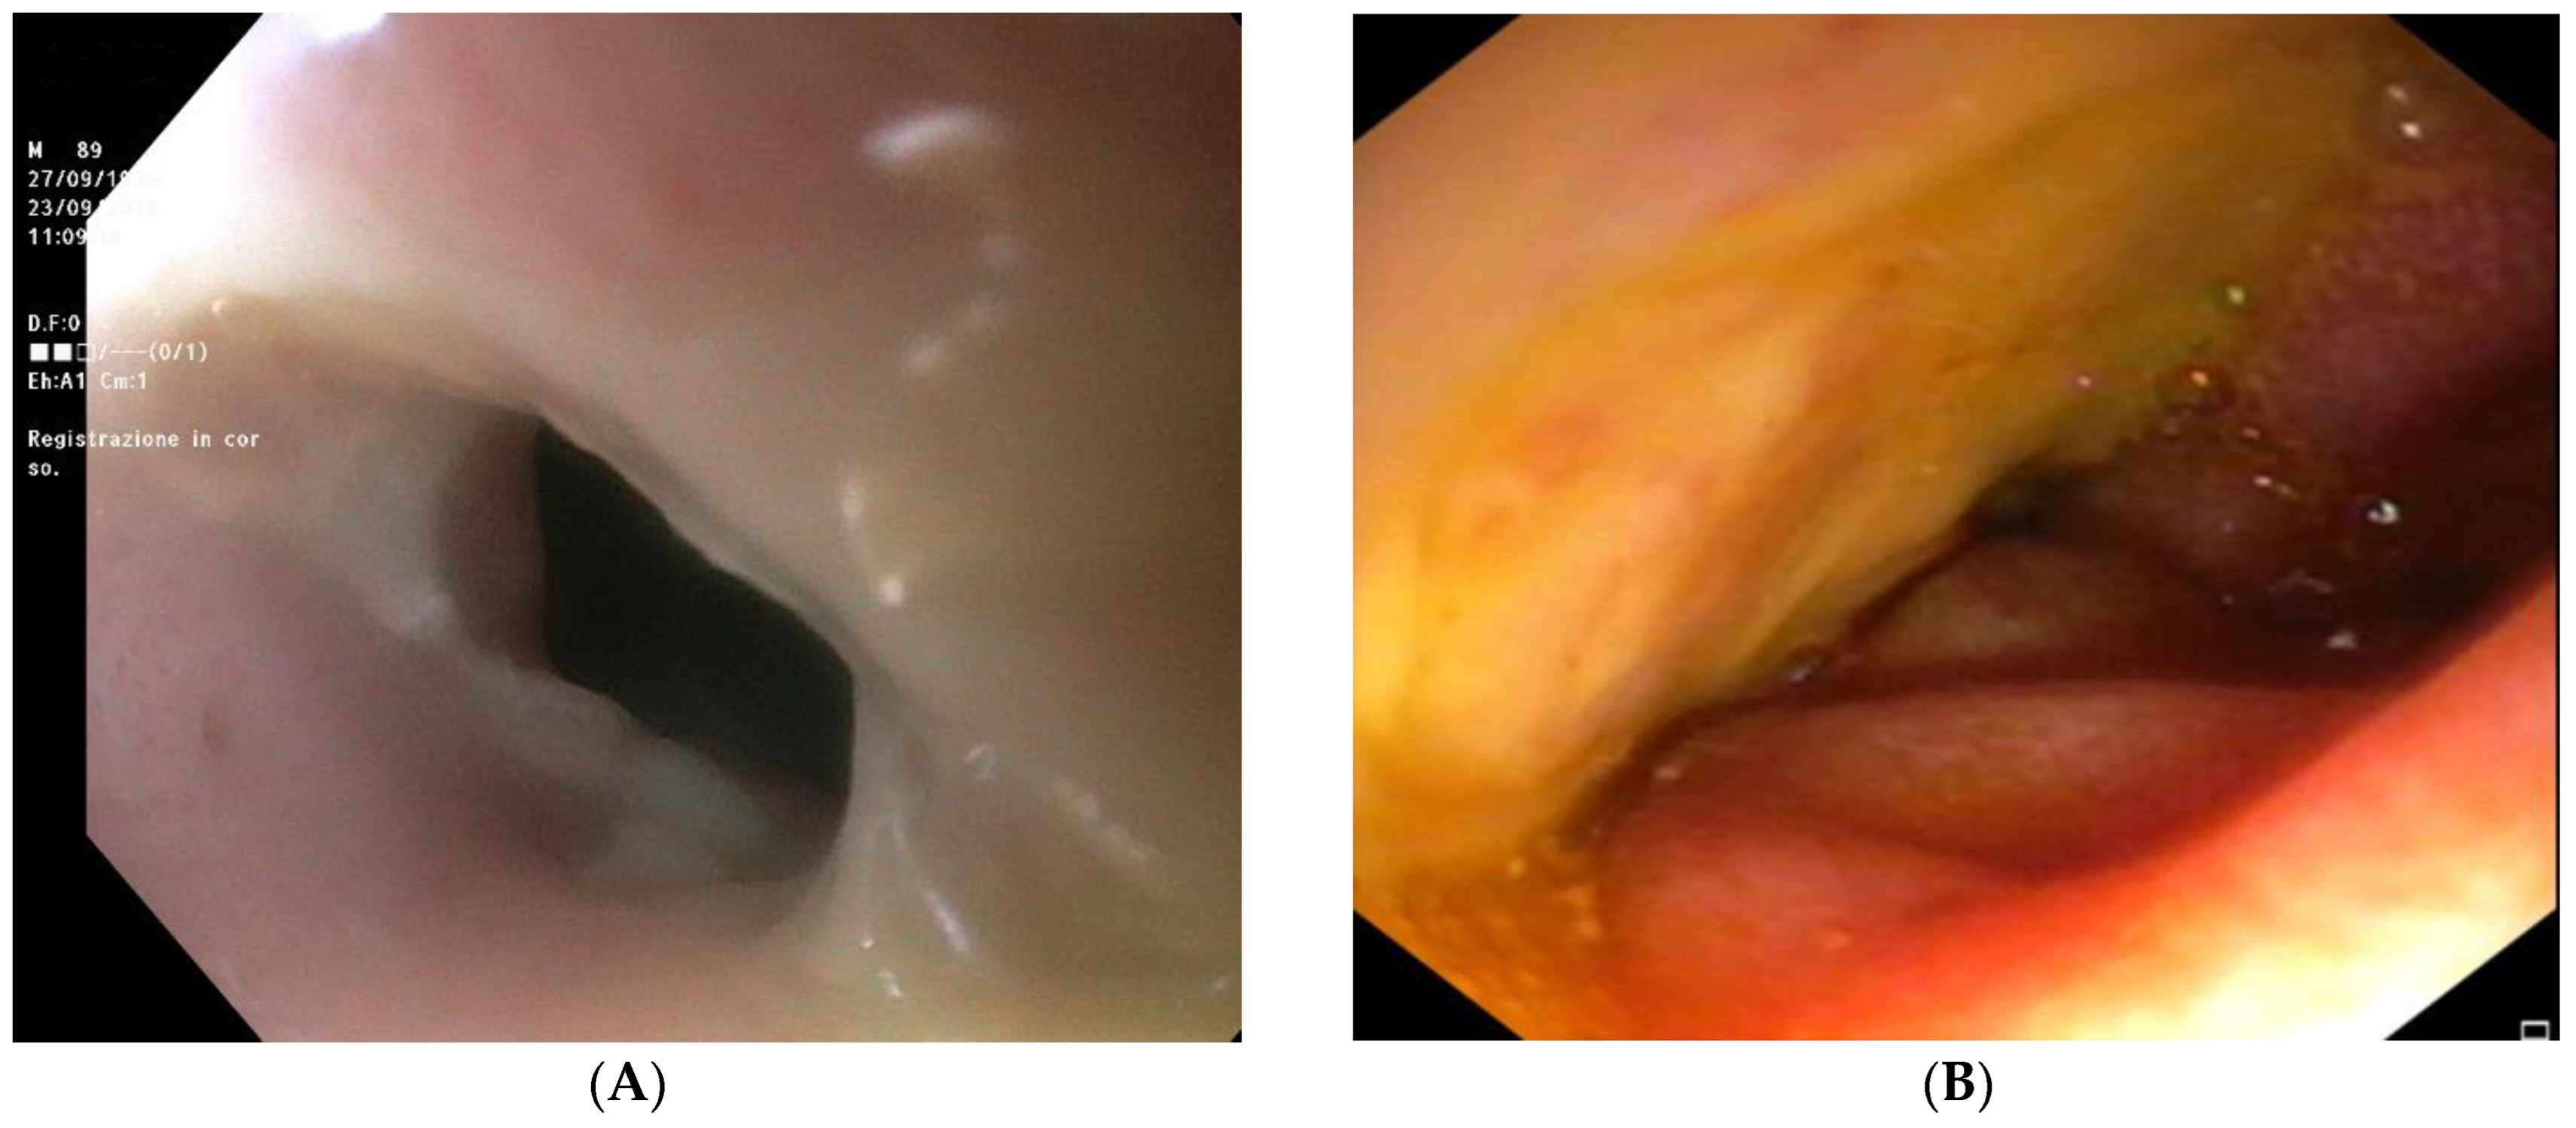

The patient was readmitted 2 months later for recurrence of coffee ground emesis. EGD revealed the presence of a distal esophageal stenosis with no signs of necrosis (Figure 3A); however, exploration of the duodenum with a 5.9 mm gastroscope showed extensive ulcerations without active bleeding (Figure 3B). The patient died a few days later due to worsening of the general condition.

Figure 3.

Esophagogastroduodenoscopy performed at second admission to the emergency department. (A) Distal esophageal stenosis without necrosis; (B) extensive ulcerations of duodenum.